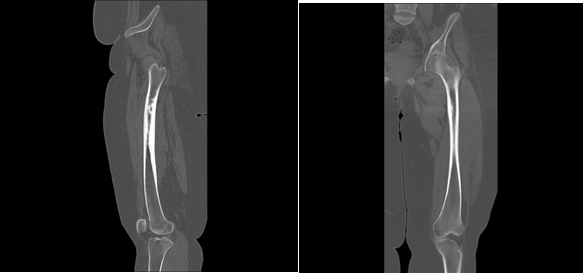

The X-ray test revealed focal cortical thickening involving the medial aspect of the femur’s proximal diaphysis, along with no definite fracture or bone lesion (Figure 1). The CT test revealed medial focal cortical thickening involving the proximal third of the femoral shaft (Figure 2).

Figure 2 CT scan of the left hip and femur show a medial focal cortical thickening involving the proximal third of the femoral shaft with loss of joint space of the hip joint.